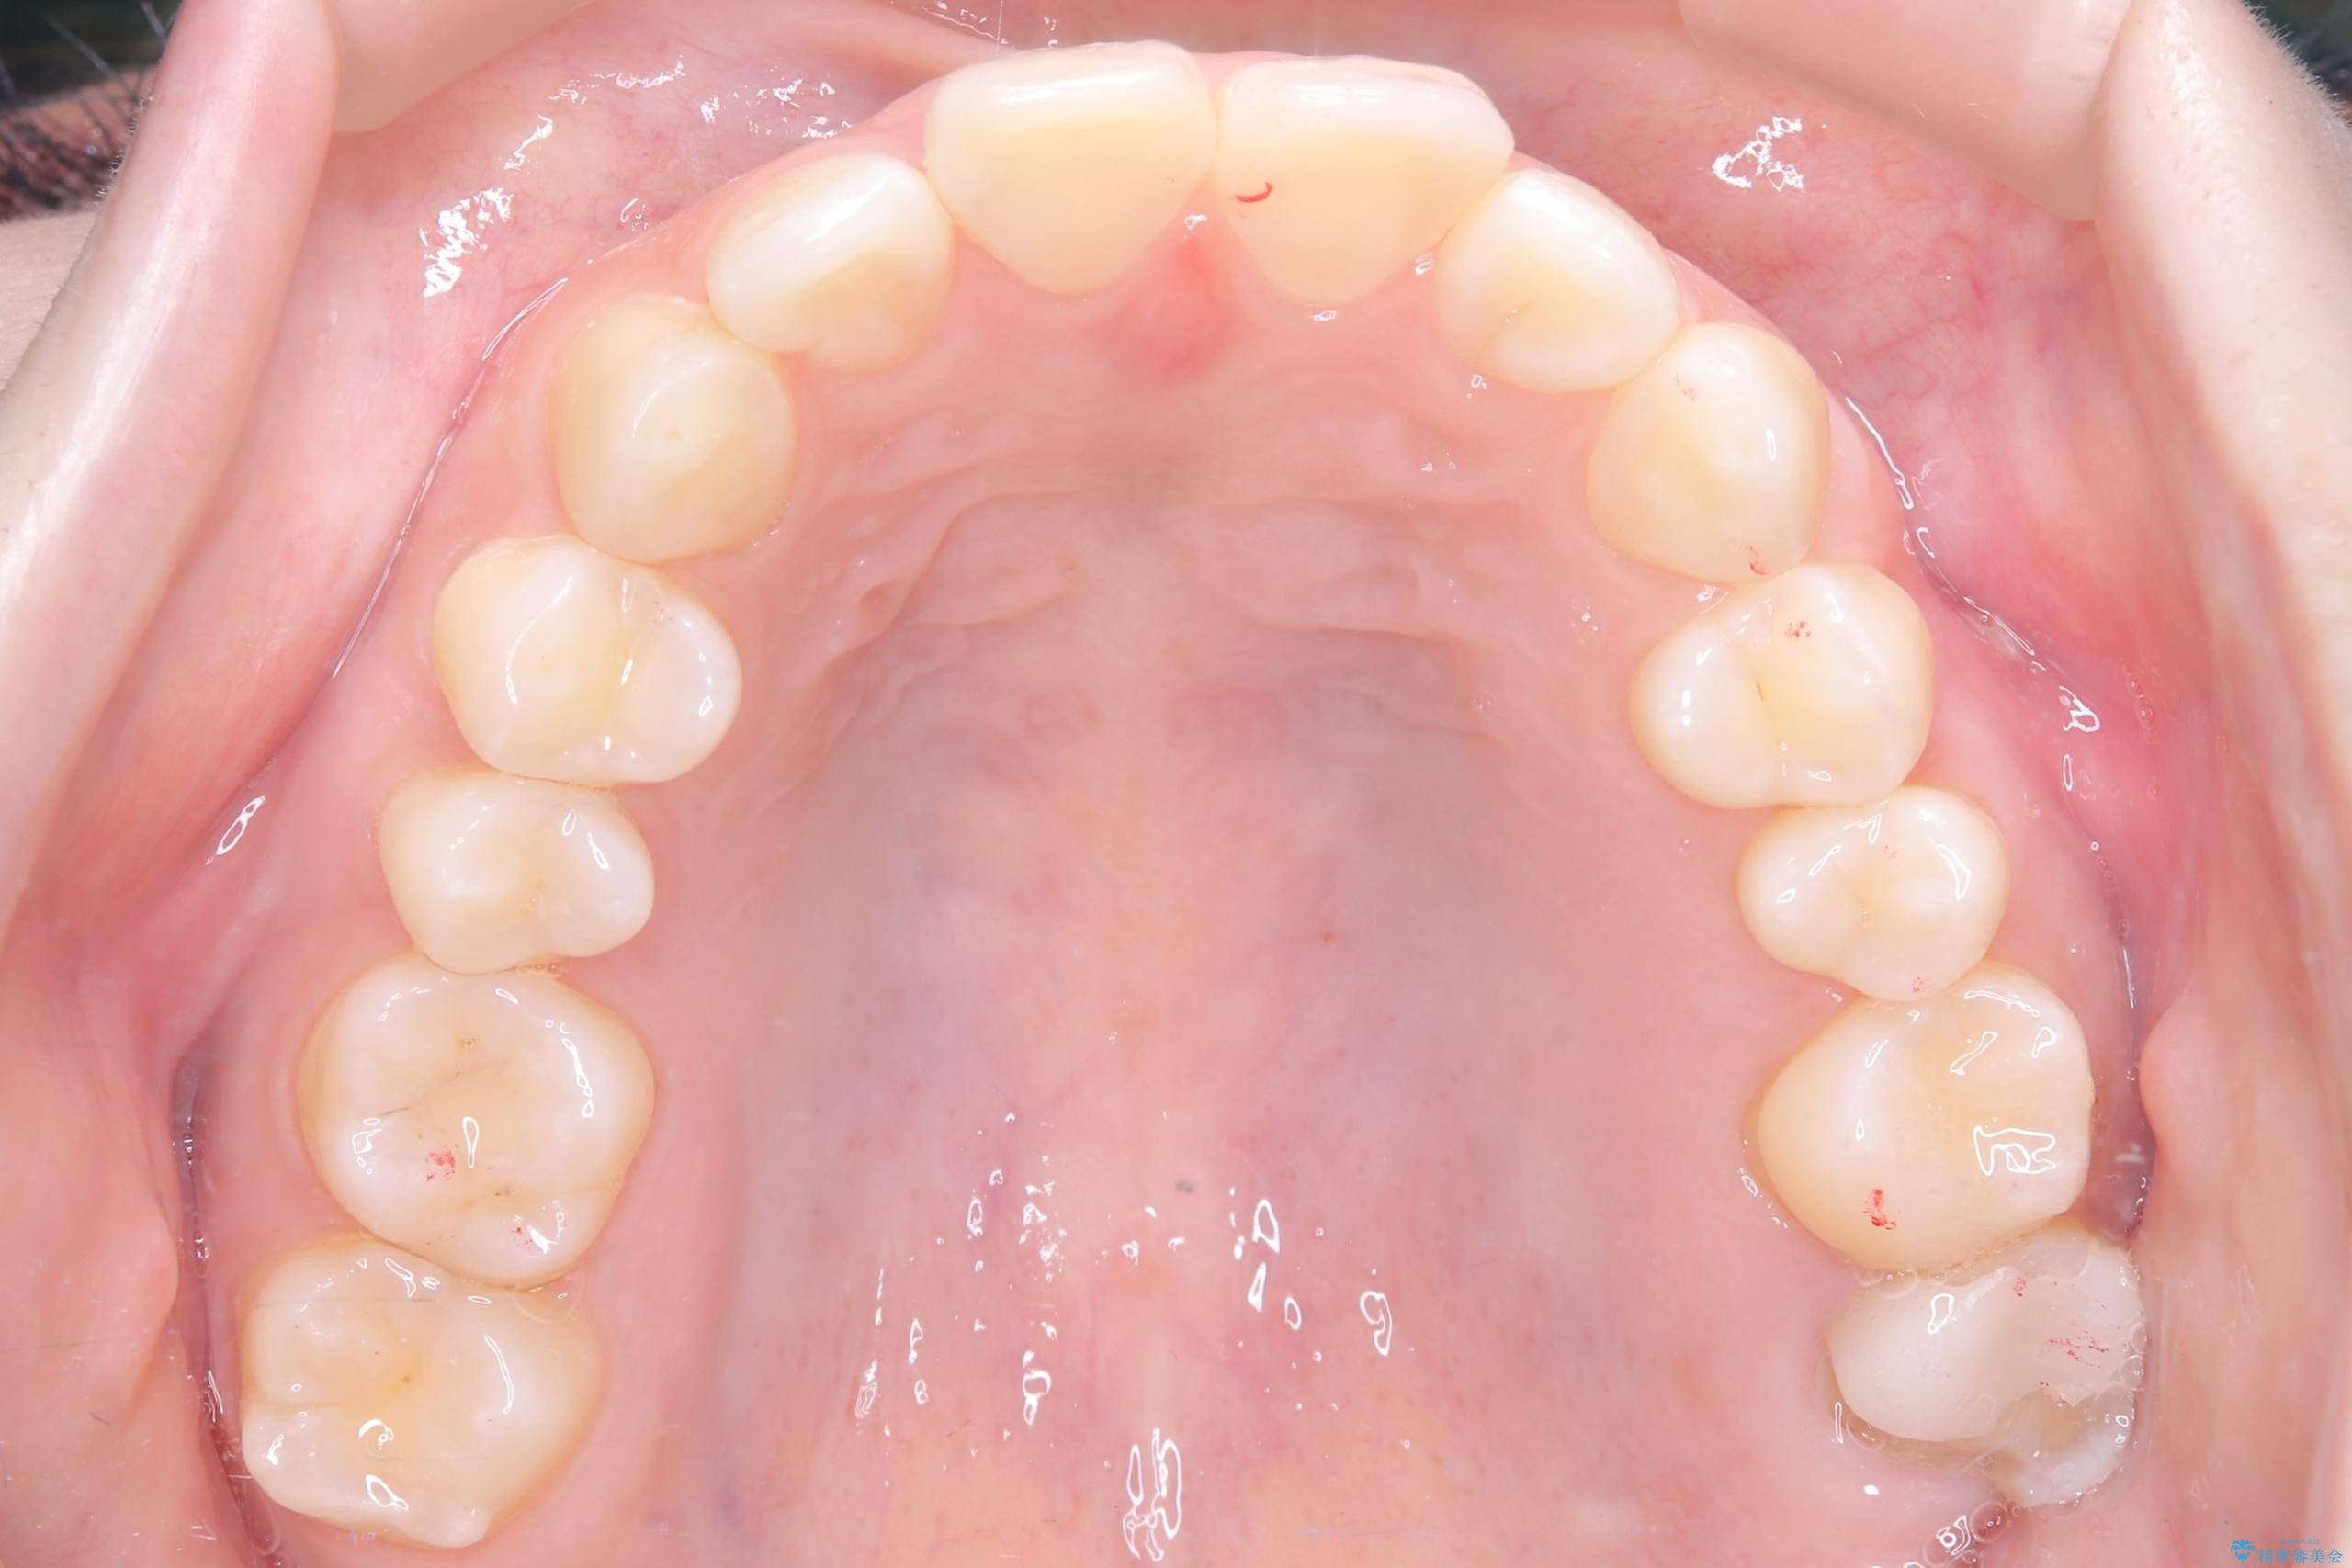

- 前歯のデコボコ(叢生)を気にされてご来院されました。精密な検査の結果、歯が並ぶスペースが不足していることが判明。患者様のご希望から、透明で目立ちにくいインビザライン(マウスピース矯正)による治療計画を立案しました。抜歯を避け、奥歯全体を奥へ動かす遠心移動という方法でスペースを確保し、前歯の叢生を解消することを目指します。

今回の矯正治療では、透明なマウスピース型の装置インビザラインを使用しました。この装置は取り外し可能で、日常生活で目立ちません。治療は、緻密に計算された計画に基づき、段階的に作製されたマウスピースを交換していくことで、奥歯から順に全体を後方へ移動させる遠心移動を実施。これにより、前歯を並べるための十分なスペースが確保され、デコボコが解消されました。抜歯することなく、機能的にも審美的にも整った美しい歯並びを獲得していただけました。